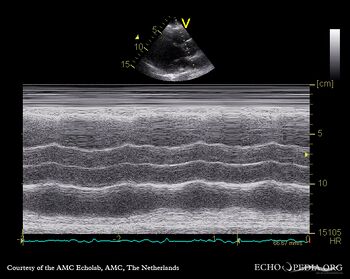

M-Mode through aortic valve: no opening of aortic valve PSAX